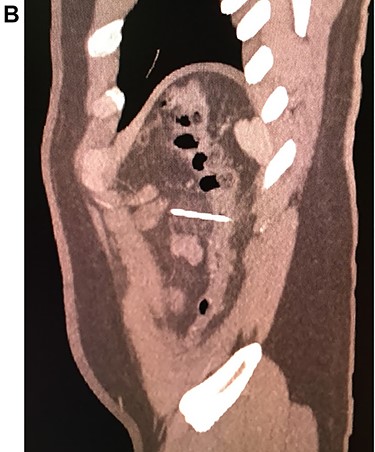

Leukocytosis with neutrophilia was detected, along with an elevated C-reactive protein. On the CT, a high-density object was seen in the descending colon; the object resembled a 4.5 cm needle that perforated the whole extent of the colonic wall. Surrounding this area there was inflammation with mesenteric edema. No lymph nodes or other masses were detected (Fig. 1A, 1B, 1C).

With these findings, surgical consultation was required, and surgery was decided on a laparoscopic approach.